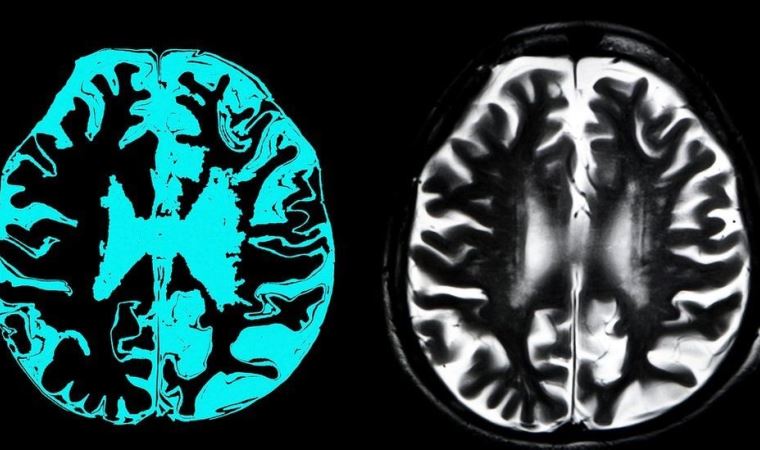

İngiltere'de yapılan araştırmalarda Covid-19 geçiren kişilerin beyninde küçülme görüldüğü saptandı. Bu doğrultuda beynin küçülmesi yani gri maddenin azalması doğrudan kişinin IQ seviyesiyle de doğru orantılı.

GRİ MADDE YA DA GRİ CEVHER NEDİR?

Beyindeki gri madde, kılcal damarların oluşturduğı merkezi sinir sisteminin önemli bir bileşenidir. Merkezi sinir sisteminde beyaz ve gri olmak üzere iki farklı madde bulunmaktadır. Sinir ağlarından oluşan beyaz made, beyinde bilgi aktarımı yapıyor.

Gri madde ise hipokampusta bulunuyor. Beynin kas dokusunun kontrölü ile ilgili bölgelerini ve görme, duyma, hafıza, duygular, konuşma, karar verme ve kendi kendini kontrol etme gibi bilişsel yetenekler ile duygusal algıları içeriyor.

Bilim insanları IQ ile doğrudan ilişkili gri maddenin son derece önemli olduğunu, insanların bilişsel yeteneklerinin tamamen buna bağlı olduğunu dile getiriyor. Örneğin düşük gri madde oranı, doğrudan zihinsel gerilik, demans ve alzheimer hastalığı ile ilişkilendiriliyor.